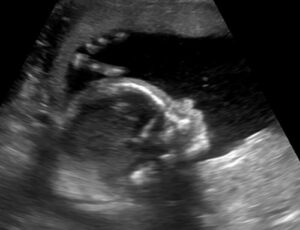

Alcuni scienziati in Germania e nel Regno Unito hanno scoperto che il ritmo del respiro della madre condiziona la sincronizzazione del suo battito cardiaco con quello del bambino che porta in grembo. Queste scoperte, riportate sulla rivista Proceedings of the National Academy of Sciences, si basano su un nuovo approccio matematico che potrebbe essere usato per rilevare complicazioni nel primo periodo della gravidanza.

Il ritmo cardiaco del feto – relativamente semplice da misurare – viene spesso usato per indicare l’attività motoria del bambino durante il secondo e il terzo trimestre di gravidanza. Studi precedenti hanno indicato che si può trovare un rapporto tra la condizione materna e quella del feto sulla base dell’osservazione del ritmo cardiaco del feto.

È stato chiesto a sei donne sane, tra la 34a e la 40a settimana di gravidanza con feto singolo, di mantenere un certo ritmo respiratorio (respirare 10, 12, 15 o 20 volte al minuto) per 5 minuti in posizione distesa. Le sessioni erano separate da intervalli di due o tre minuti. Per registrare l’attività cardiaca della madre e del feto è stato usato un magnetocardiografo. Questo strumento non invasivo rileva i campi magnetici generati dall’attivazione del muscolo cardiaco e non provoca alcuno stress alla madre o al feto.